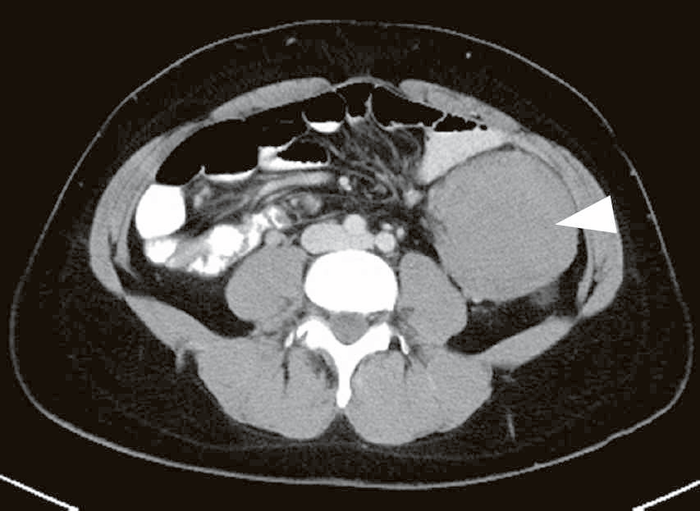

- デスモイド腫瘍(図Ⅱ-12)は,FAP患者の8~20%に認められ37,110-112),線維腫の一種で,転移はしないが浸潤性に発育する傾向がある。

図Ⅱ-12 腹腔内デスモイド腫瘍(▽)